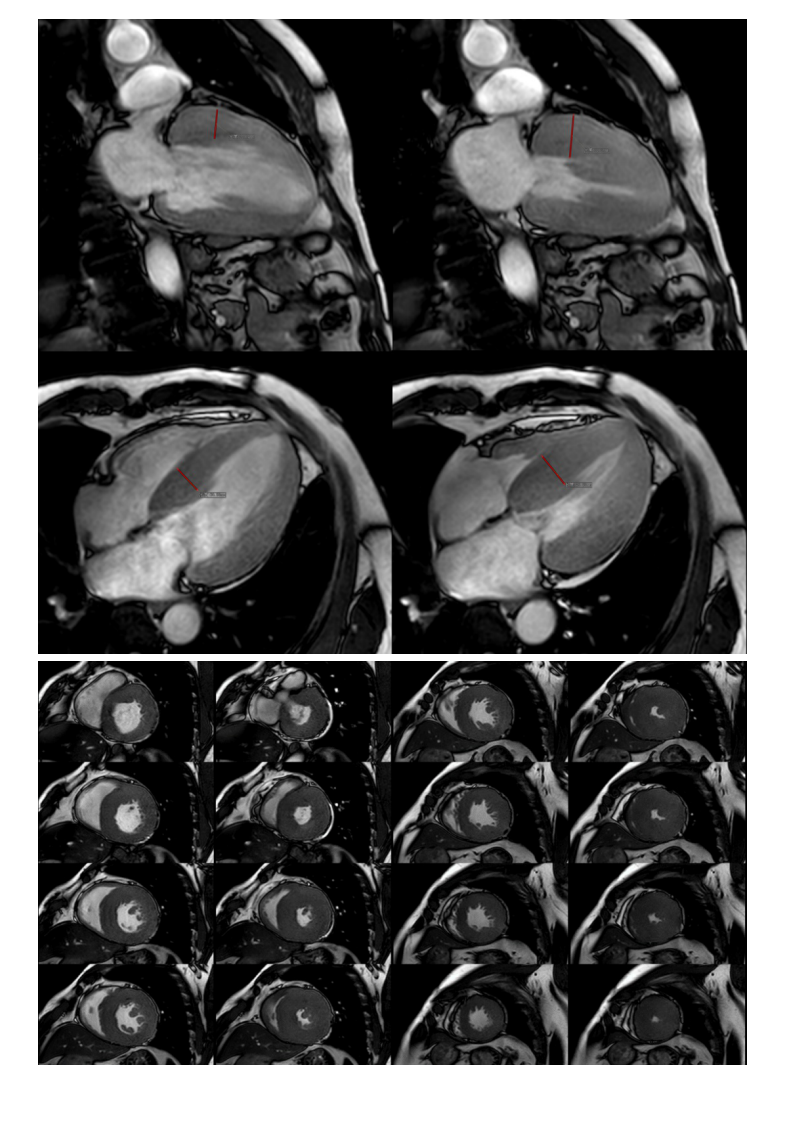

20210601_3【晨读结果公布】2021.05.31循环系统疾病——病例1:肥厚型心肌病;病例2:主动脉瓣膜病变继发改变.pdf